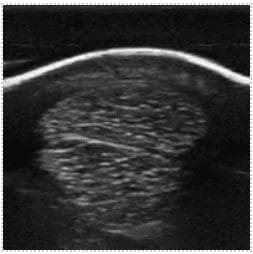

A. In short, yes! Incredibly so, in fact. It is important to note that they have been designed with a specific purpose in mind. Namely, point-of-care ultrasound (POCUS), and the flexibility they offer is, frankly, stunning. Typically, they offer two or more transducer options. Either by virtue of interchangeable ‘heads’, or being ‘double-ended’, with different transducer types on each end. Wireless transmission of image data to a smart device (phone, tablet, etc.) enables viewing anywhere, and image quality is surprisingly good. They wouldn’t replace a traditional high-end system, certainly, but in the context of the relatively recent rise in popularity of POCUS, they are something of a game-changer. Light, portable, robust, low-cost, and high-quality, I suspect it won’t be long before they’re as ubiquitous and indispensable as a stethoscope.

Canine kidney, GE Vscan Air Equine SDFT & DDFT, GE Vscan Air